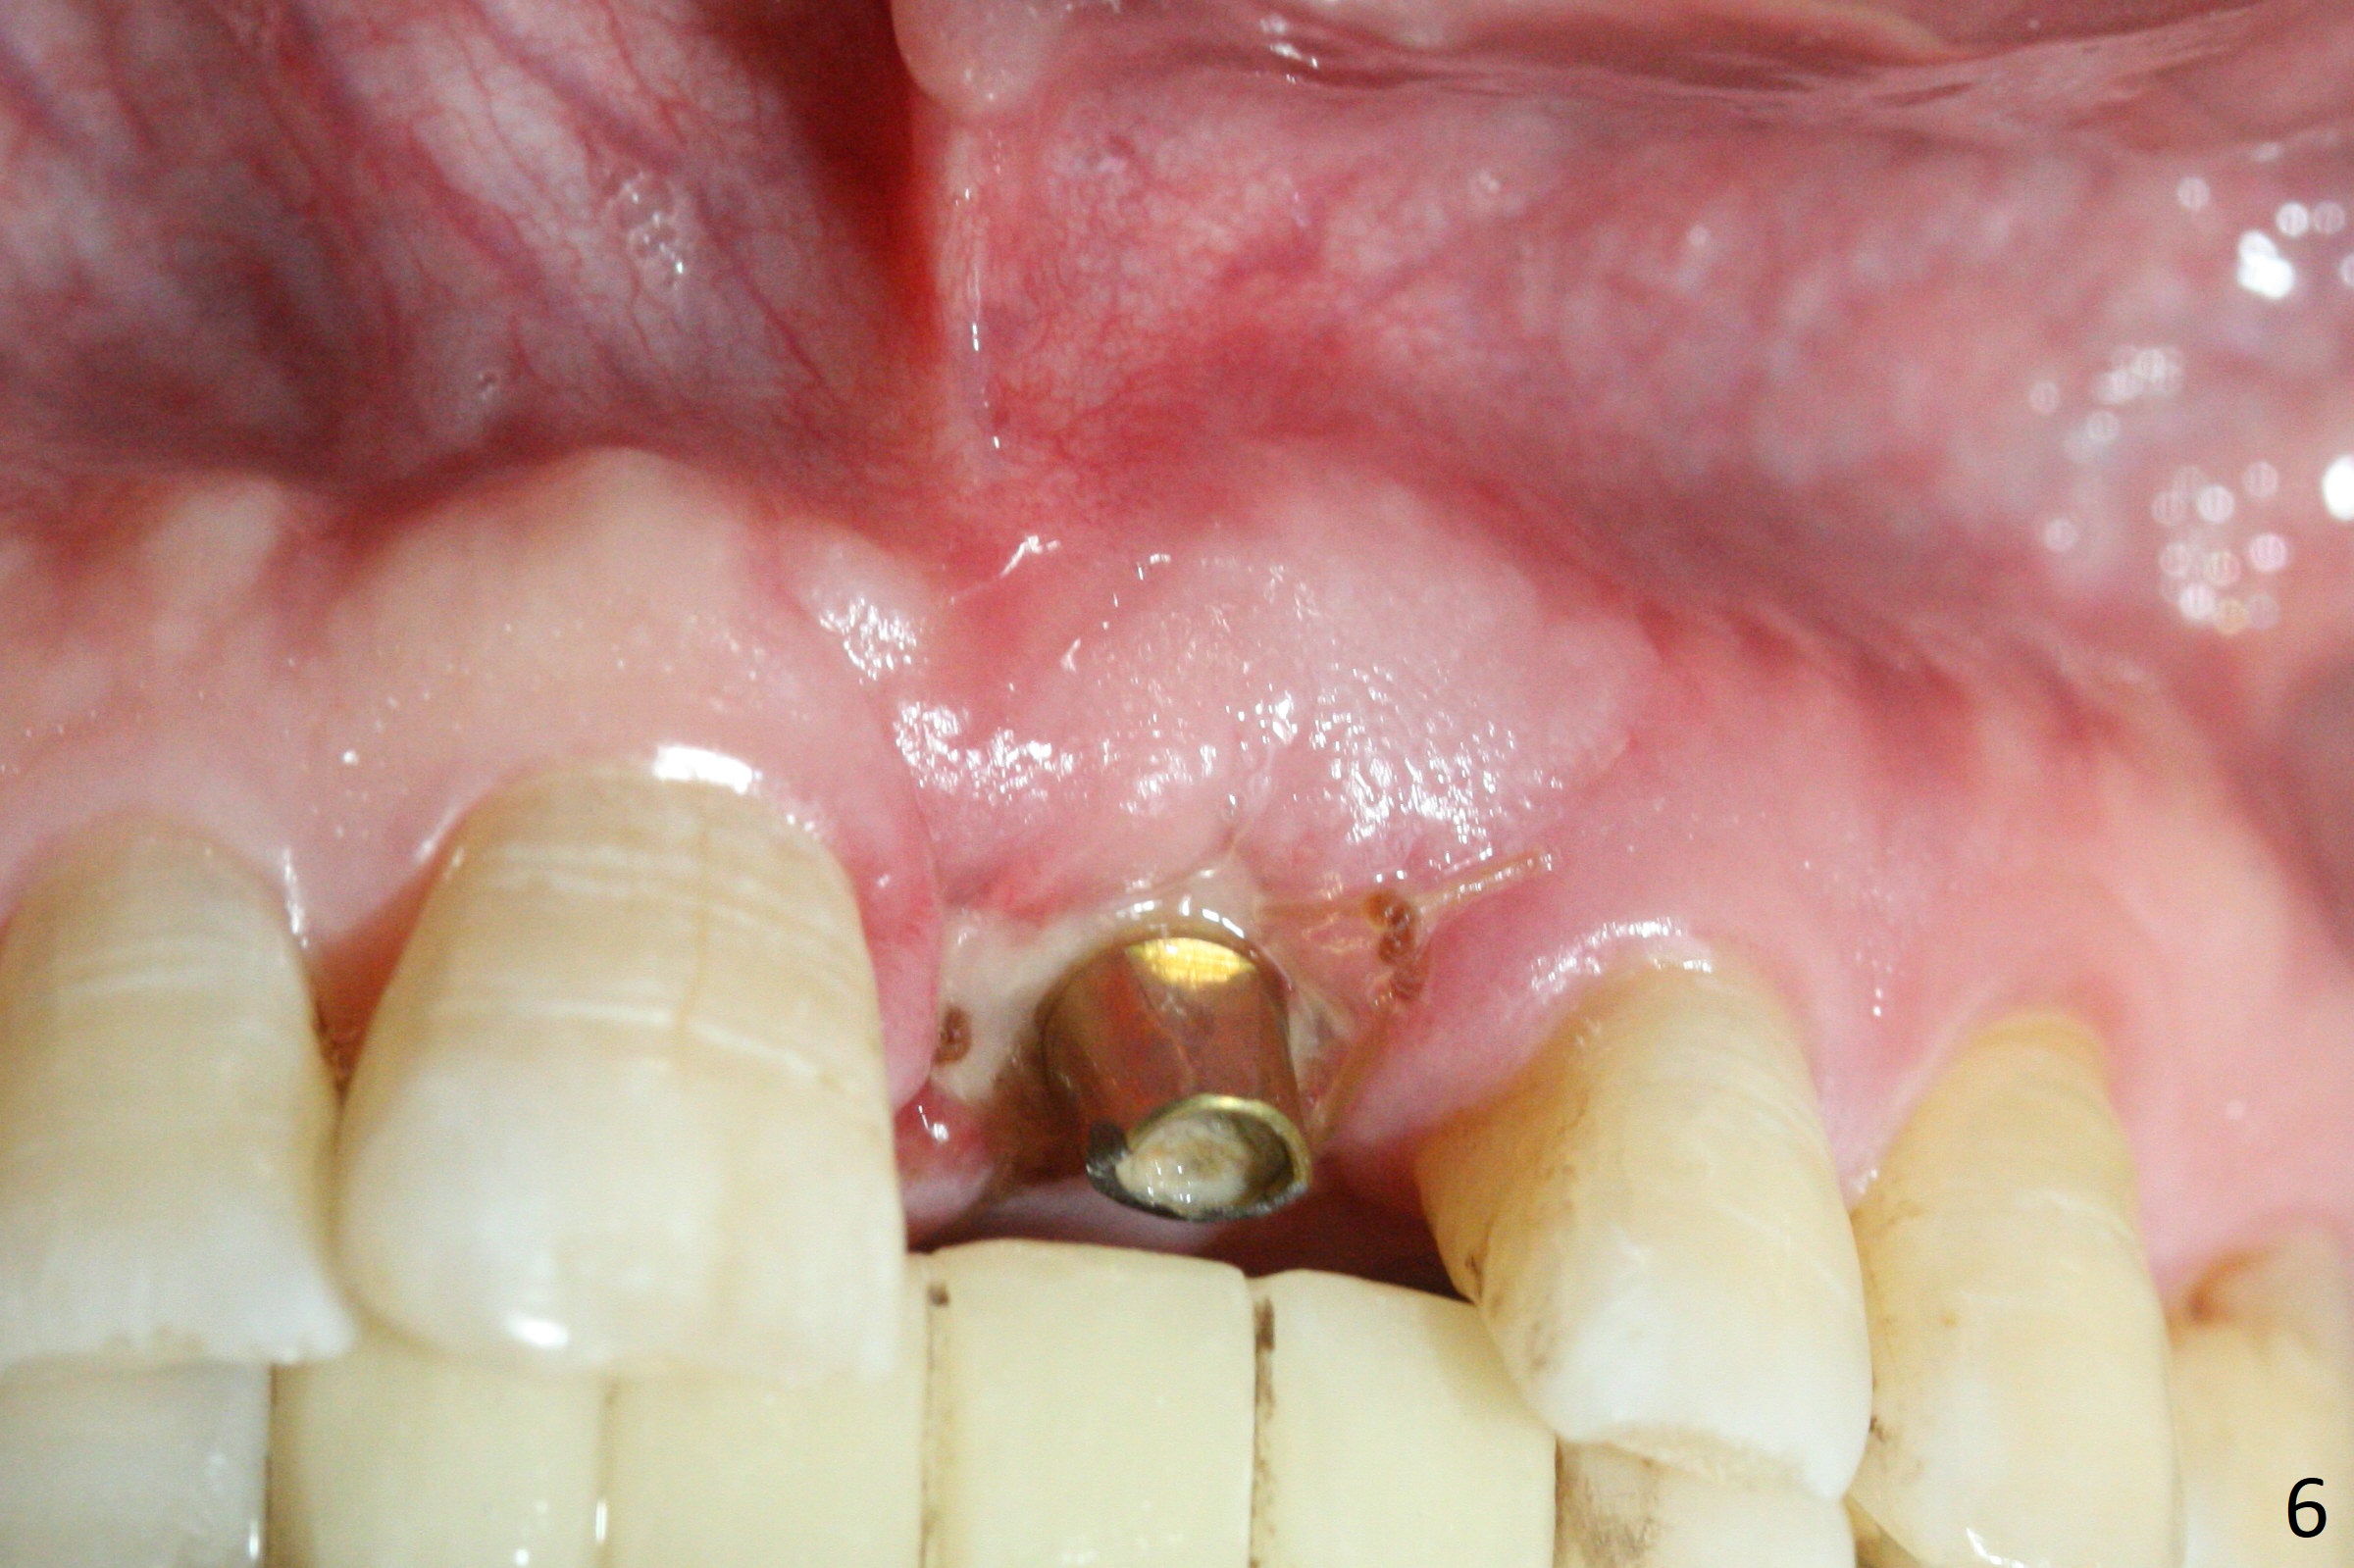

Preop examination shows mobility I of the teeth #8 and 10 and apparent occlusal trauma from #22-26 implant bridge. After occlusal equilibrium, incision reveals low, but moderate ridge at #9 (Fig.1). Fig.2a is a cross section of a normal upper incisor socket with thin buccal plate (B) and thick palatal one (P). It is difficult to initiate osteotomy in the oblique palatal wall when the buccal plate is resorbed (Fig.2b). In this case with horizontal buccal and palatal plate bone loss, the socket bottom is flat (Fig.2c), easy for osteotomy (Fig.2d green arrow, Fig.3). The initial osteotomy deviates mesial (Fig.3). To avoid perforation into the Incisive Canal, the trajectory is changed (Fig.4). After use of the final drill (3 mm), the coronal Incisive Canal is perforated. Following placement of a 3.5x13 mm implant and 4.5x5.5(4) mm abutment, Vanilla Graft is placed (Fig.5 *) to repair the perforation. Retrospectively, the coronal end of the Incisive Canal is revealed at incision (Fig.1 *). The initial osteotomy should be slightly more distal (Fig.3 black line). The buccal plate looks bulky due to placement of the abutment and bone graft 1 week postop (Fig.6,7 (crown dislodgement)). The bone graft appears to remain in place 2 months postop (Fig.8). Impression is taken because of instability of the immediate provisional (Fig.9 after Laser gingivectomy). The gingiva and buccal plate remain healthy 4.5 months postop (Fig.10). A permanent crown is cemented (Fig.11).